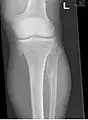

ورم عظمي غضروفي متعدد حول الركبة

يعتمد تشخيص HMO على إنشاء ارتباط دقيق بين السمات السريرية المذكورة أعلاه وسمات الصور الإشعاعية المميزة. يمكن أن يوفر تاريخ العائلة دليلًا مهمًا للتشخيص. يتم استكمال هذا عن طريق اختبار الجينين حيث من المعروف أن المتغيرات المسببة لHMO هما EXT1 وEXT2. مزيج من تحليل التسلسل وتحليل الحذف لمناطق الترميز بأكملها لكل من EXT1 وEXT2 يكشف المتغيرات المسببة للأمراض في 70% -95% من الأفراد المتضررين.[3][4] السمة المميزة للتشخيص الشعاعي هي وجود أورام عظمية غضروفية في النهايات كردوس للعظام الطويلة التي تمثل فيها القشرة النخاعية والنخاع العظمي امتدادًا مستمرًا للعظم المضيف. يتضح هذا بسهولة في الصور الشعاعية للركبتين.[1]